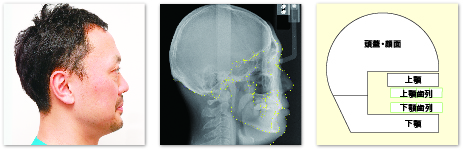

骨格性とは、頭の骨に対する上顎・下顎の位置関係や上下顎骨の位置関係の分析になります。歯は上顎・下顎それぞれの上に並んでいるので、歯が並ぶ土台である上顎・下顎の骨格の位置が、歯並びに最も大きな影響を与えます。したがって骨格の分析が非常に重要になります。

このように顎骨や歯といった硬組織だけではなく、周囲の筋肉(主に口唇)などとのバランス、調和を評価し診断することが重要になります。これらの分析を行う上で最も重要なのがセファロ(頭部X線規格写真)です。

セファロについて

矯正歯科の検査を受けられた方の中には、「なぜ歯科でこれほど大きな頭部全体のレントゲンを撮らなければいけないんだろう」と疑問に思うこともあるかもしれません。しかし、セファロは、これらの原因を分析するために最も重要な検査になります。